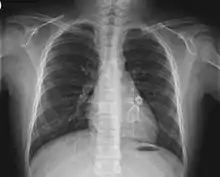

Heart complications are the most important aspect of Kawasaki disease, which is the leading cause of heart disease acquired in childhood in the United States and Japan.[30] In developed nations, it appears to have replaced acute rheumatic fever as the most common cause of acquired heart disease in children.[14] Coronary artery aneurysms occur as a sequela of the vasculitis in 20–25% of untreated children.[51] It is first detected at a mean of 10 days of illness and the peak frequency of coronary artery dilation or aneurysms occurs within four weeks of onset.[47] Aneurysms are classified into small (internal diameter of vessel wall <5 mm), medium (diameter ranging from 5–8 mm), and giant (diameter > 8 mm).[30] Saccular and fusiform aneurysms usually develop between 18 and 25 days after the onset of illness.[14]

Even when treated with high-dose IVIG regimens within the first 10 days of illness, 5% of children with Kawasaki disease develop at the least transient coronary artery dilation and 1% develop giant aneurysms.[52][53][54] Death can occur either due to myocardial infarction secondary to blood clot formation in a coronary artery aneurysm or to rupture of a large coronary artery aneurysm. Death is most common two to 12 weeks after the onset of illness.[14]

Many risk factors predicting coronary artery aneurysms have been identified,[20] including persistent fever after IVIG therapy,[55][56] low hemoglobin concentrations, low albumin concentrations, high white-blood-cell count, high band count, high CRP concentrations, male sex, and age less than one year.[57] Coronary artery lesions resulting from Kawasaki disease change dynamically with time.[3] Resolution one to two years after the onset of the disease has been observed in half of vessels with coronary aneurysms.[58][59] Narrowing of the coronary artery, which occurs as a result of the healing process of the vessel wall, often leads to significant obstruction of the blood vessel and the heart not receiving enough blood and oxygen.[58] This can eventually lead to heart muscle tissue death, i.e., myocardial infarction (MI).[58]

- Echocardiogram may show subtle coronary artery changes or, later, true aneurysms.

- Angiography was historically used to detect coronary artery aneurysms, and remains the gold standard for their detection, but is rarely used today unless coronary artery aneurysms have already been detected by echocardiography.